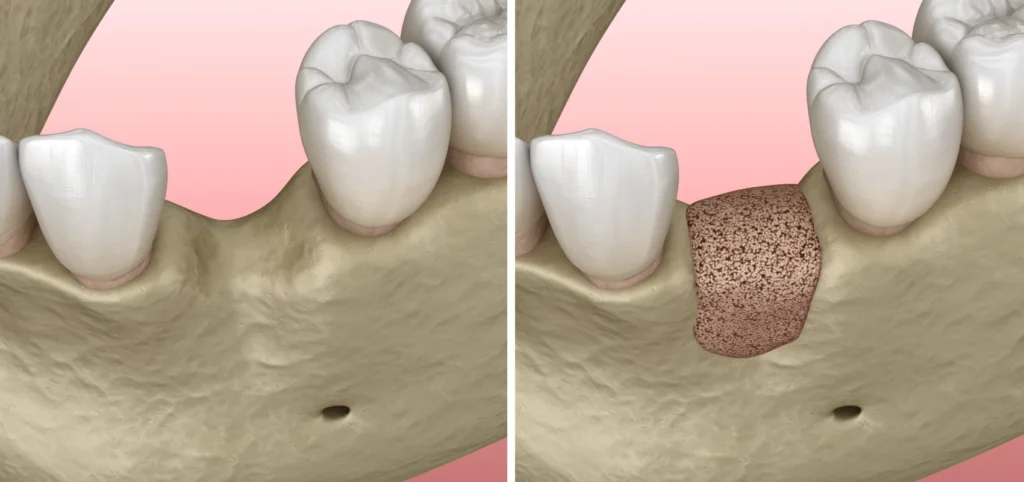

Les greffes osseuses font aujourd’hui des techniques courantes en implantologie. Elles permettent de faire face à un déficit en volume osseux (en hauteur et/ou en épaisseur) lorsque nous devons poser un ou plusieurs implants.

- Le scanner réalisé au cabinet met en évidence un défaut osseux majeur nécessitant une greffe osseuse complexe pour réhabiliter la zone par 2 implants.

- Il s’agit de prélever un greffon osseux dans la zone postérieure de la machoire inférieure de la patiente. Ce greffon est ensuite modelé et transfixé avec des vis au niveau du site à traiter.